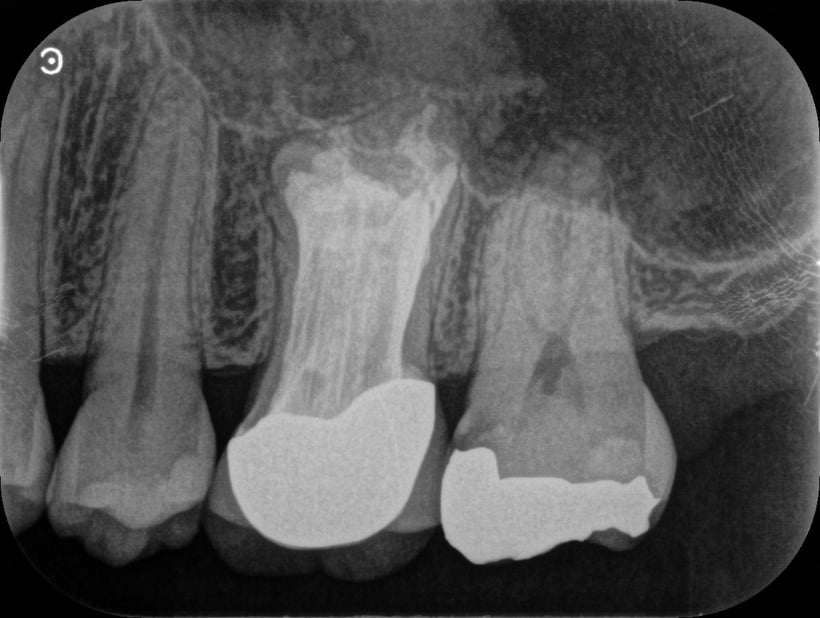

歯根の周囲には、歯根を取り巻くようなX線透過があります。(炎症があるということです)

根管の中には、ガッタパーチャという天然ゴムの根管充填材がありますが、これが緊密に歯根の尖端まで充填(詰め)されていないので、このような状態となっています。まずは、このガッタパーチャを完全に除去することが重要です。